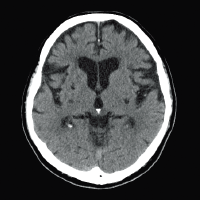

Cerebral infarction

Lacunar infarction

Clinical images with Intelli IP

Head routine